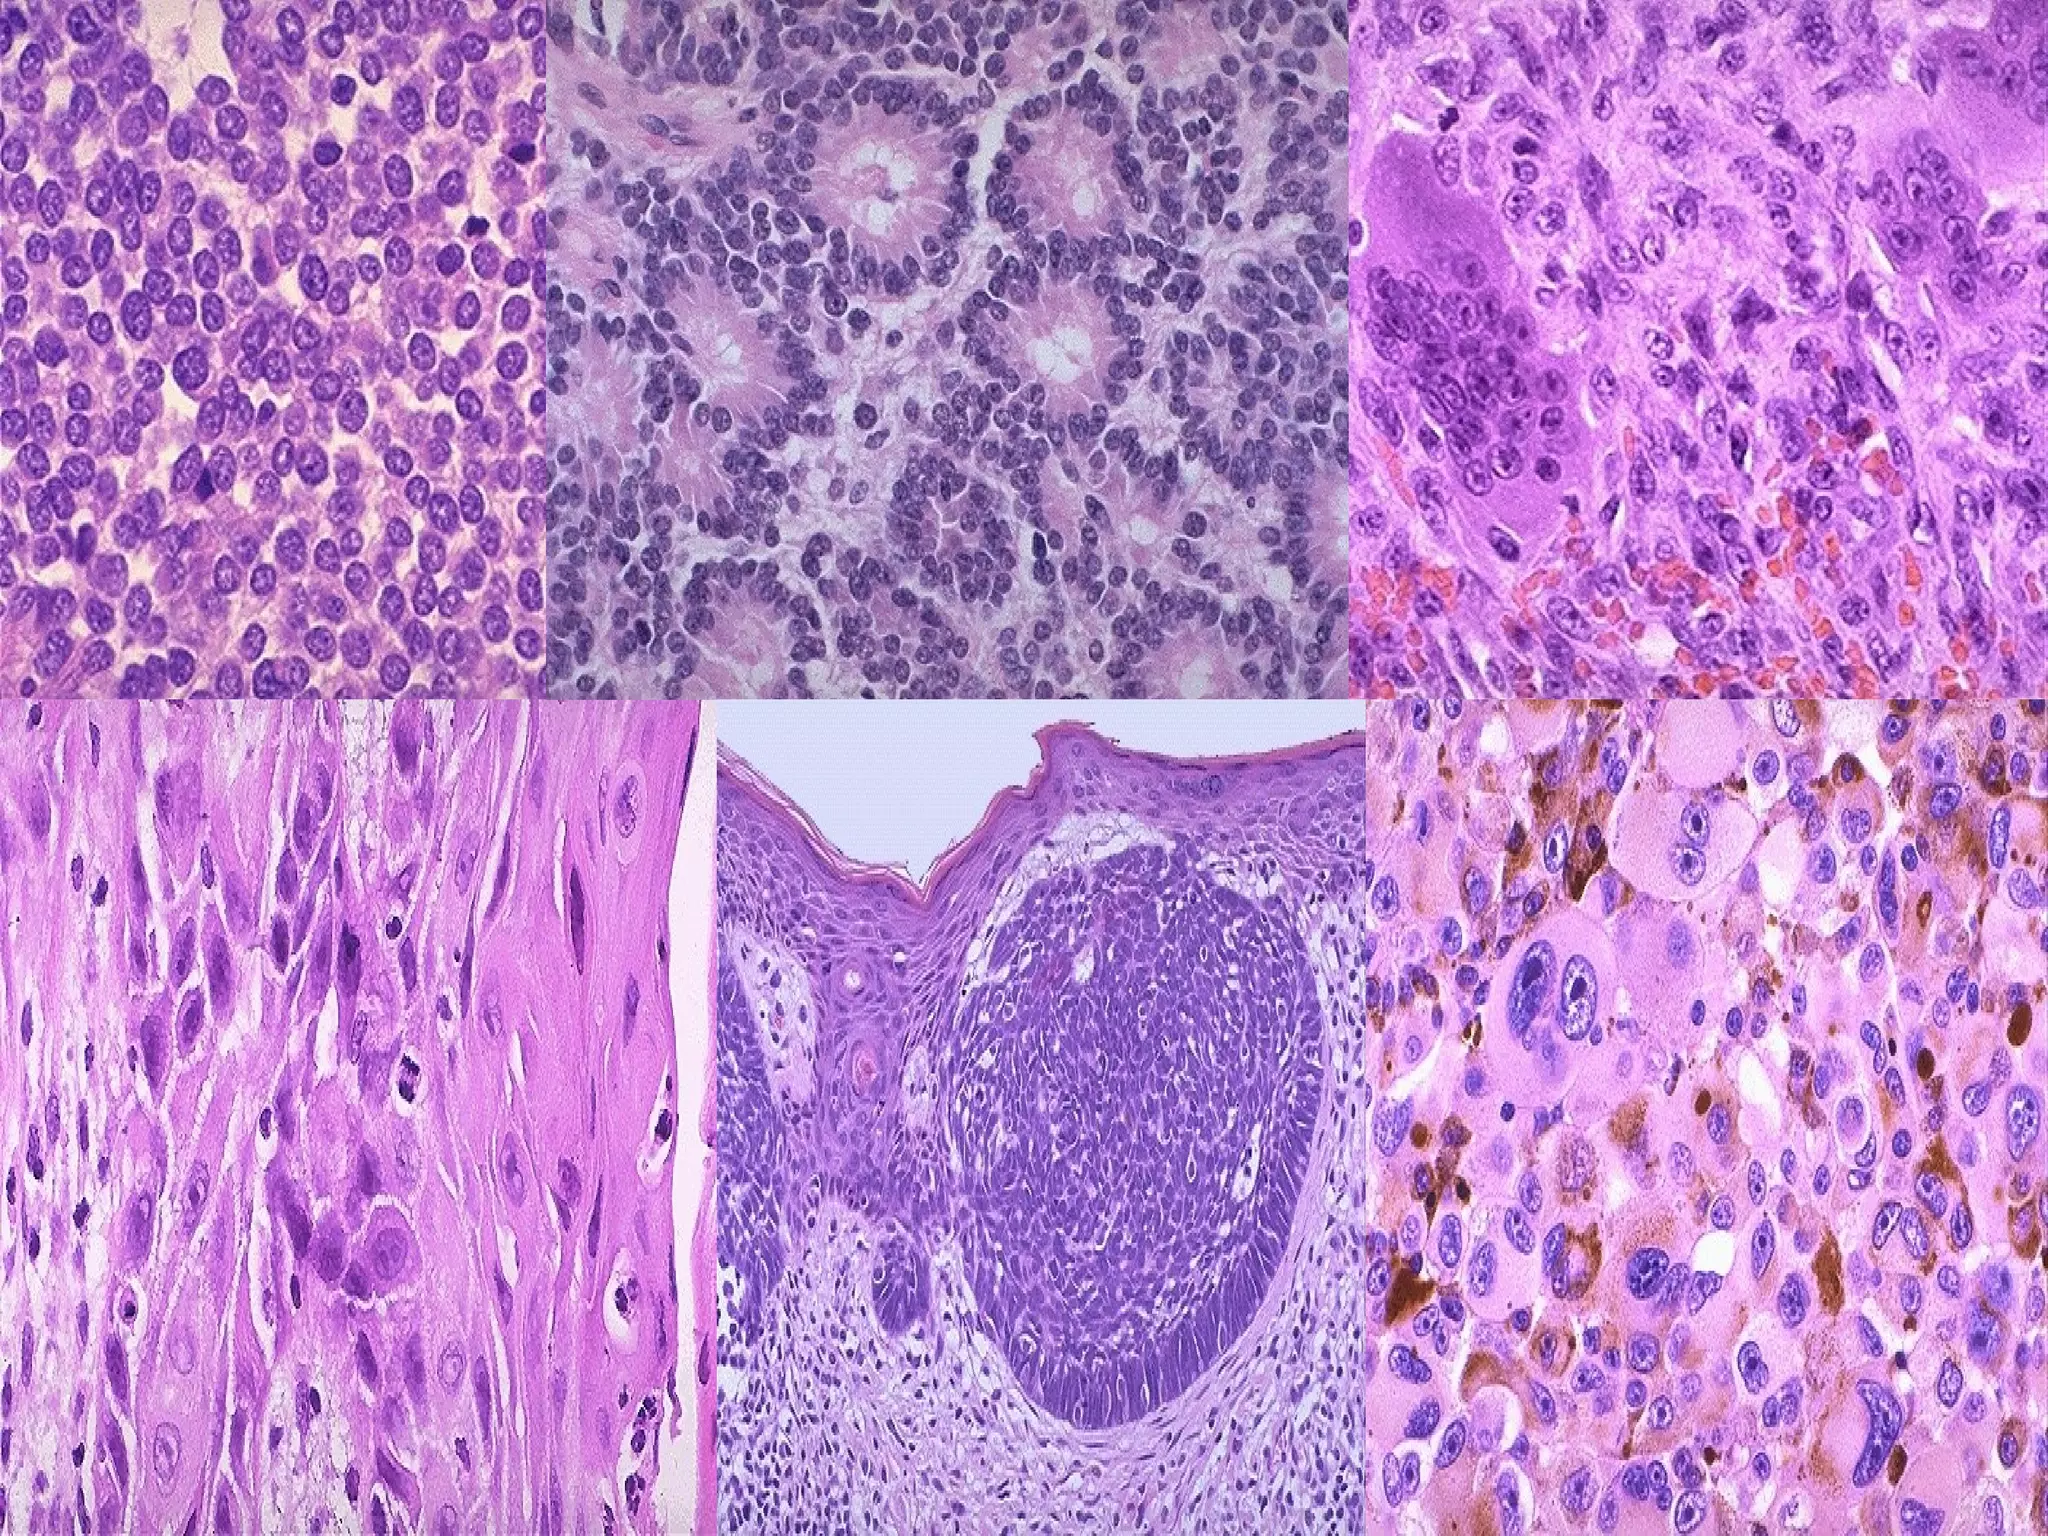

Neoplasia Classification Ppt Document neoplasia.pptx, subject nursing, from egerton university, length: 59 pages. Explore the world of neoplasia, from benign to malignant tumors, differentiation, growth rates, and more. learn how neoplasms impact patients and the intricate classifications. Description : check out this medical presentation on cancer titled "neoplasia" to know about the characteristics of neoplasms compared to normal tissues, types of neoplasms (benign vs malignant, cellular differentiation, and classification schemes), and the genetic basis for neoplasia. Tumor nomenclature lecture objectives • define neoplasia, and explain what makes a neoplastic cell different from a non neoplastic cell. • list several characteristics of benign and malignant tumors.

Neoplasia Classification Ppt Description : check out this medical presentation on cancer titled "neoplasia" to know about the characteristics of neoplasms compared to normal tissues, types of neoplasms (benign vs malignant, cellular differentiation, and classification schemes), and the genetic basis for neoplasia. Tumor nomenclature lecture objectives • define neoplasia, and explain what makes a neoplastic cell different from a non neoplastic cell. • list several characteristics of benign and malignant tumors. Summary benign tumors are well differentiated, circumscribed encapsulated and never metastasize. malignant tumors show lack of differentiation, local invasion and metastasis. Most tumors initially develop as monoclonal, arising from a single mutated cell. Download neoplasia pathology lecture slides and more pathology slides in pdf only on docsity!. What is neoplasia? a neoplasm is defined as a genetic disorder of cell growth that is triggered by mutations affecting a single cell and its clonal progeny.